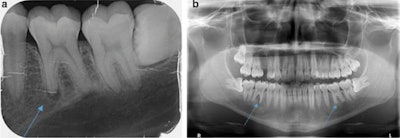

The patient's routine x-ray taken by a primary dentist in January 2019 reveals that tooth #36 and #46 showed no signs of apical osteolysis before the intense bruxism started. The teeth also did not show visible signs of caries or fillings. All images courtesy of Gund et al. Licensed by CC BY 4.0.A percussion test was negative, and the exam and imaging revealed no anomalies, pulp calcifications, or formation defects of the hard tooth tissue. Also, there was no external resorption, root canal, or pulp chamber perforation, according to the report.

a: An x-ray taken in October 2019 shows apical osteolysis in tooth #36. b: An x-ray taken in October 2019 shows apical osteolysis in tooth #36 and #46. The osteolysis is greater in tooth #46.Then, two and a half months later, the patient's pain returned, prompting his primary dentist to take a new x-ray. This dentist diagnosed him with apical periodontitis on tooth #36 and #46, and he began endodontic treatment even though the teeth already appeared dead, the authors wrote.